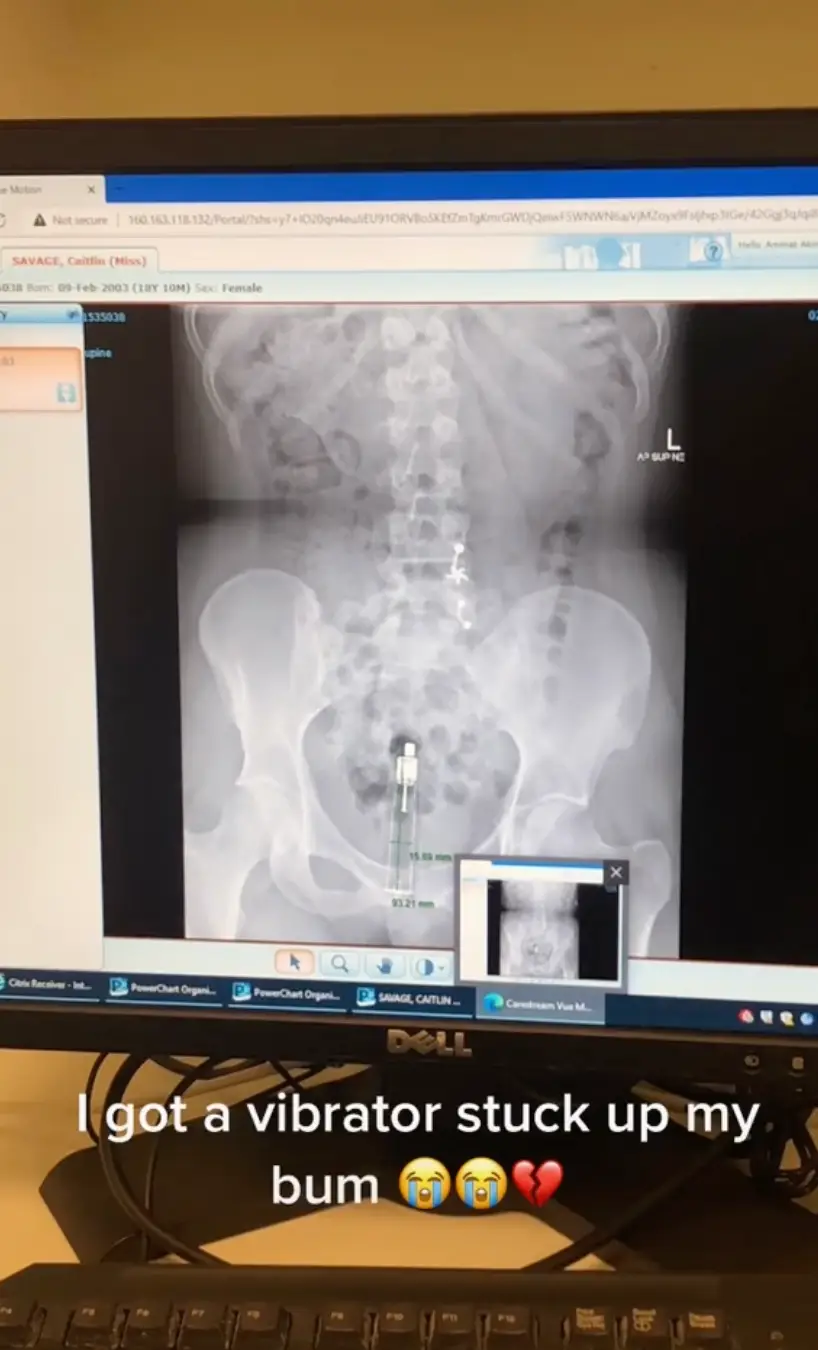

The video was set to Jay-Z's hit '99 Problems' and began with a selfie from Caitlin before quickly cutting to an x-ray of the vibrator inside her.

She rhymed the lyrics 'I got 99 problems, but a b*tch ain't one,' with the caption: "I got vibrator stuck up my bum."